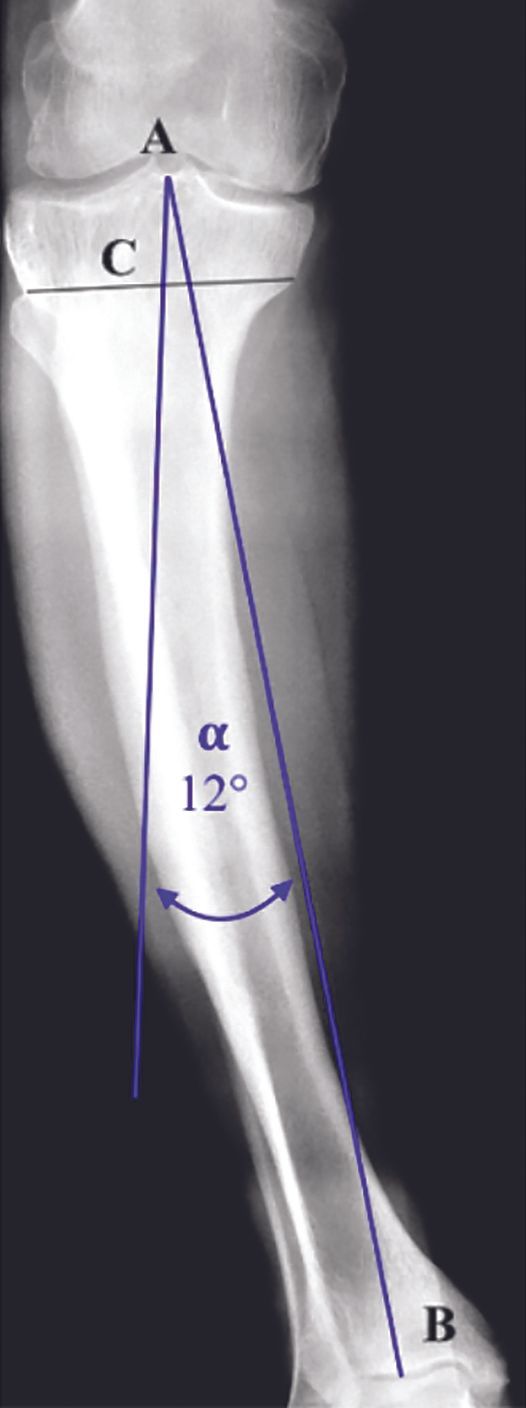

Mise au point Choix de la contrainte dans les grandes déformations en varus , Axel Schmidt Service de chirurgie orthopédique, Hôpital de la Croix-Rousse, Lyon, France , Elliot Sappey-Marinier Hôpital de la Croix-Rousse, Hospices Civils de Lyon, Lyon, France , Elvire Servien Hôpital de la Croix-Rousse - HCL, Service de chirurgie orthopédique et de médecine du sport, FIFA medical center of excellence, Lyon, France N°297 - Octobre 2020 ● 14 min de lecture